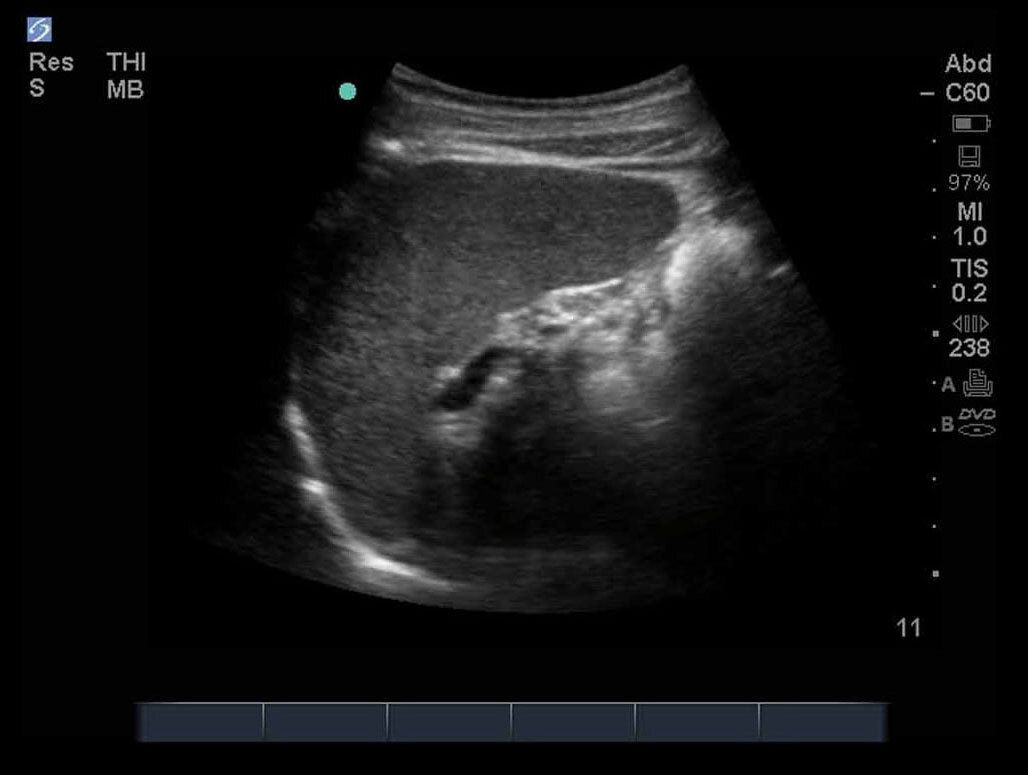

FAST 左上四半部 (LUQ) 3 画像

M-Turbo:FAST検査、左上四半部 3。